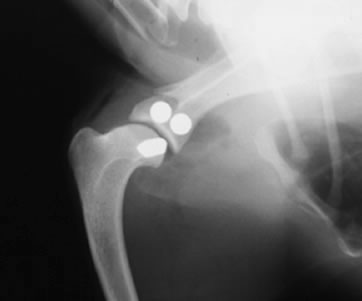

肘関節形成不全症 / UAP(肘突起分離症)

肘関節形成不全症 / UAP(肘突起分離症)とは

肘突起の 肘頭への癒合障害により痛みが生じます。

診断

レントゲン検査、関節鏡検査

治療

分離した肘突起の肘頭への固定、分離した肘突起の切除